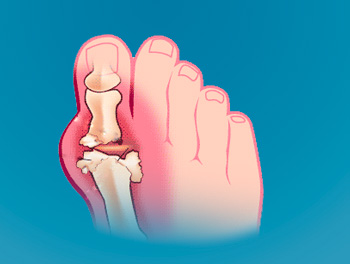

Началом подагры принято считать первый приступ артрита. В 50-70% случаев артрит начинается с первого плюсне-фалангового сустава на ноге, но первично могут поражаться и другие суставы. Нередко приступу подагры предшествуют предвестники: отсутствие аппетита, изжога, плохой вкус во рту, общая слабость, судороги в икроножных мышцах, чувство тревоги, озноб, дизурические явления. Боль быстро нарастает, иногда за считанные минуты, при этом она бывает настолько сильной, что прикосновения простыни мучительны для больного. Кожа над поражённым суставом блестящая, напряжённая, горячая на ощупь. Отмечается резкая болезненность при прикосновении и малейших движениях. Подагрический приступ может сопровождаться повышением температуры, общей слабостью, ознобом, потливостью, жаждой, тошнотой.

В основе острого приступа подагры лежит артрит, возникающий как реакция суставной ткани на осаждение кристаллических уратов, вызывающих воспаление сустава. Первый суставной приступ знаменует начало подагры. Вторая суставная атака может возникнуть через несколько месяцев или даже лет. Но без соответствующего лечения подагры, атаки артрита становятся всё чаще, время ремиссии сокращается, удлиняется приступ, иногда до 1-2 месяцев, в процесс вовлекаются новые суставы, в них появляются стойкие изменения, характерные для деформирующего артроза. Наступает следующий период – хронический. Боли в суставах становятся почти постоянными.